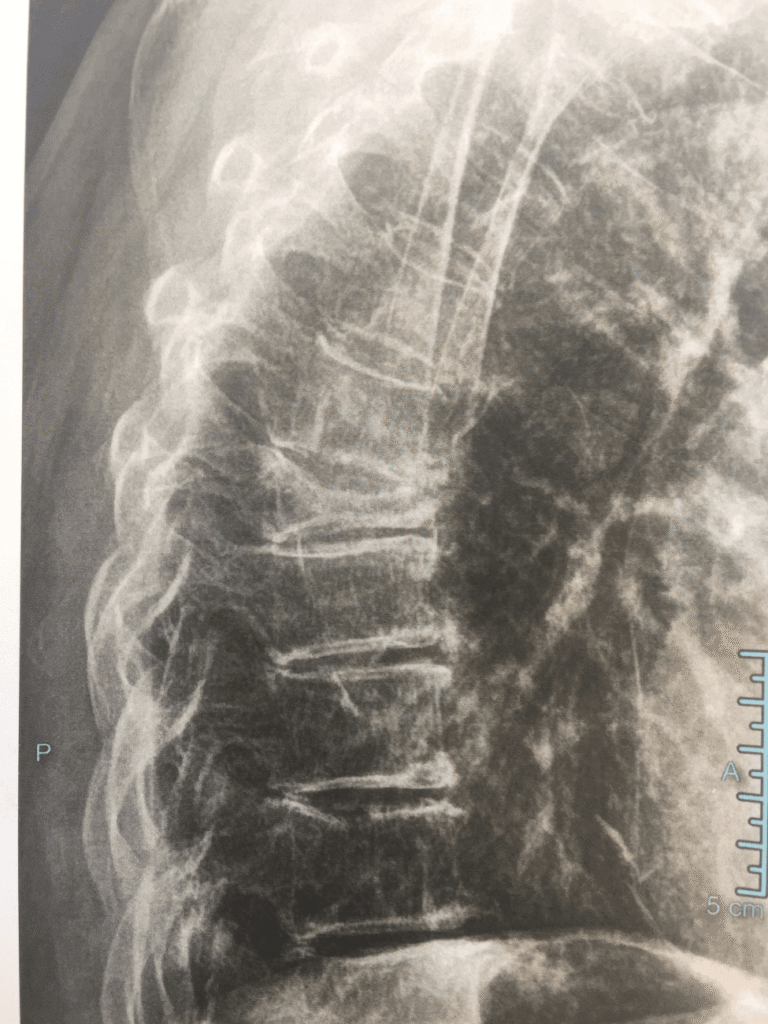

- Wirbelkörperfrakturen (Keil-, Fisch-, Kompressionsfrakturen → Rundrücken, Größenverlust)

- Bildgebung: Röntgen (Wirbelkörperfrakturen)

- Wirbelkörperfrakturen → Kyphose, Größenverlust